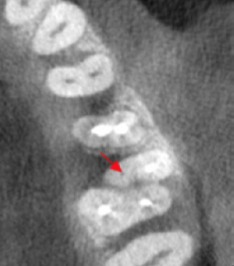

Fig 2. Axial CBCT slice of maxillary left quadrant. Note missed MB2 canal of tooth #14. (1)